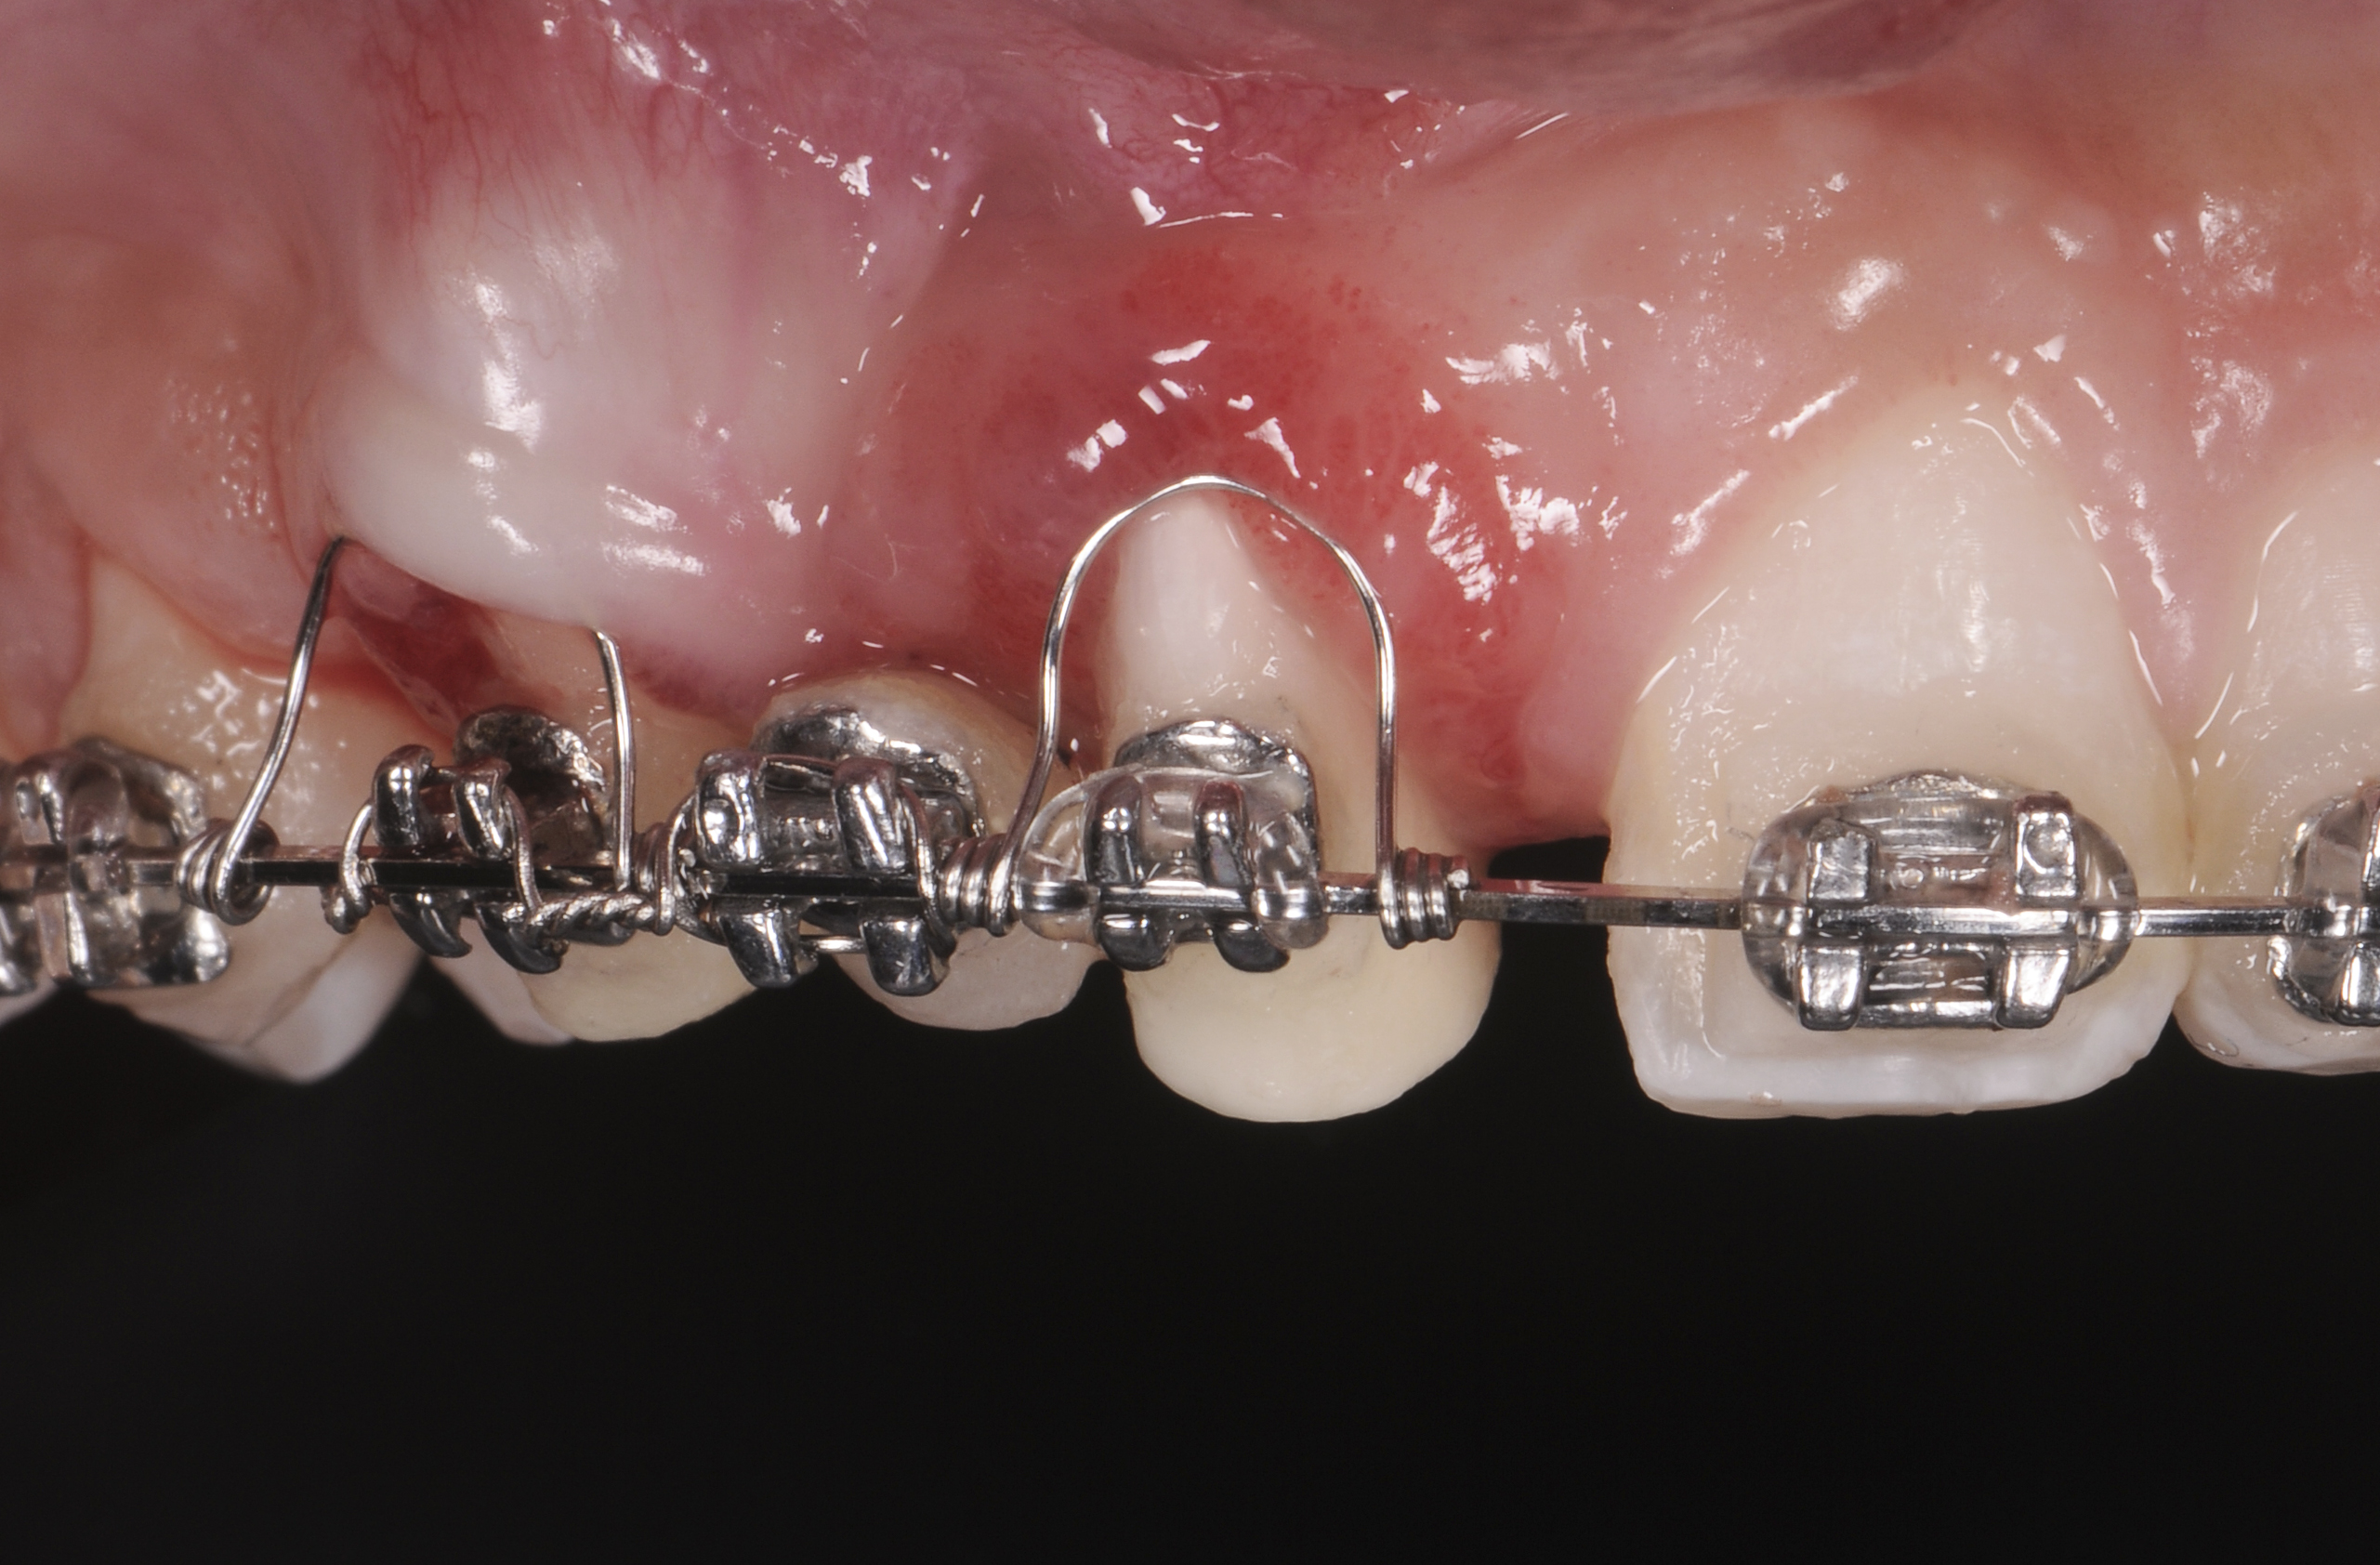

Successful outcomes with forced eruption require the establishment of treatment endpoints, which may include overcompensation beyond the desired soft- and hard-tissue changes. For the present case, achieving ideal gingival-alveolar socket architecture required force-erupting tooth No. 6 to the level of the apical third and tooth No. 8 beyond the confines of its alveolus. As the gingival sulcus is everted through the eruption process, a gingival red patch corresponding to the nonkeratinized sulcular epithelium may appear, as shown around tooth No. 8 in Figure 8 and Figure 9. This tissue will develop into keratinized gingiva when exposed to the oral environment.31,32 Additionally, when forced eruption of this magnitude is performed, there may be a tendency for lingual displacement that needs to be addressed with root-torquing orthodontic auxiliaries (Figure 6 and Figure 7).

When forced eruption is completed, the teeth should be splinted for a 3-month stabilization period,30 which will allow mineralization of osteoid tissue and settling of the gingival remodeling process. The degree of forced eruption in the present case was such that extreme mobility precluded the use of a provisional restoration. Instead, a metal-reinforced direct composite splint extending from teeth Nos. 6 to 8 was fabricated in situ (Figure 8 and Figure 9). When compared with the preoperative condition (Figure 2), Figure 8 and Figure 9 depict the treatment progression with forced eruption. The restoration of adequate alveolar height was achieved while enhancing the soft-tissue architecture, and the everted sulcular epithelium on tooth No. 8 proceeded to develop keratinization. However, the pre-existing defect still manifested itself in the form of a residual cleft.

Fig 5. Start of orthodontic forced eruption to develop sites Nos. 6 and 8 before implant placement. A denture tooth was common-tied to the archwire to serve as a pontic. Anchorage requirements determined the extent of bracket placement.

Figure 5

Fig 6. Eruption of tooth No. 6 to the apical third and tooth No. 8 beyond its alveolus was needed to achieve ideal site development. This degree of forced eruption often results in lingual displacement that needs to be managed with root-torquing auxiliaries. Sulcular epithelium eversion can be observed on tooth No. 8.

Figure 6

Fig 7. Eruption of tooth No. 6 to the apical third and tooth No. 8 beyond its alveolus was needed to achieve ideal site development. This degree of forced eruption often results in lingual displacement that needs to be managed with root-torquing auxiliaries. Sulcular epithelium eversion can be observed on tooth No. 8.

Figure 7

Fig 8. Compared to the preoperative view seen in Fig 2, adequate alveolar height and gingival profile were achieved with forced eruption (Fig 8). Direct composite splint would remain for 3 months. Residual cleft was a visible remnant of iatrogenic defect. Post-orthodontically, keratinization of sulcular epithelium on tooth No. 8 was evident (Fig 9).

Figure 8

Fig 9. Compared to the preoperative view seen in Fig 2, adequate alveolar height and gingival profile were achieved with forced eruption (Fig 8). Direct composite splint would remain for 3 months. Residual cleft was a visible remnant of iatrogenic defect. Post-orthodontically, keratinization of sulcular epithelium on tooth No. 8 was evident (Fig 9).

Figure 9